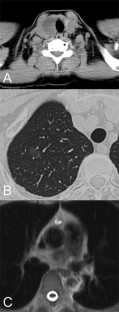

A 66-year-old woman was referred to our institute for an enlarging tumor of the thyroid, and neck and chest computed tomography scan showed not only a thyroid tumor, but also an anterior mediastinal tumor and ground-glass nodules in the lung. Because of persisting symptoms, an enlarging thyroid mass, and the possibility of cancer, excision of the tumors was proposed. A 6-cm-long vertical skin incision was made in the right axilla, a mini-thoracotomy was made in the third intercostal space, and an additional port was placed in the fifth intercostal space. Thoracoscopic partial resection of the right upper lobe of the lung was performed first. Then, the da Vinci surgical system (da Vinci, Intuitive Surgical Inc., Sunnyvale, CA, USA) was introduced through the mini-thoracotomy. The mediastinal tumor was then excised circumferentially robotically. After resection of the lung and mediastinal tumors, the da Vinci was undocked, and a subcutaneous tunnel from the axillary incision to the thyroid was created using the flap dissection technique. The da Vinci was re-introduced through the axillary incision. A long camera port was used, and the skin and muscle flap was elevated to maintain adequate working space during the robot-assisted thyroidectomy. Total operating time was 277 min, and the patient’s postoperative course was uneventful. The histopathological examinations of the lung, mediastinal, and thyroid tumors were adenocarcinoma, thymolipoma, and adenomatous goiter, respectively. In conclusion, single-incision robotic surgery for three lesions was achieved safely with good clinical results and excellent cosmetic results.

Fig. 1